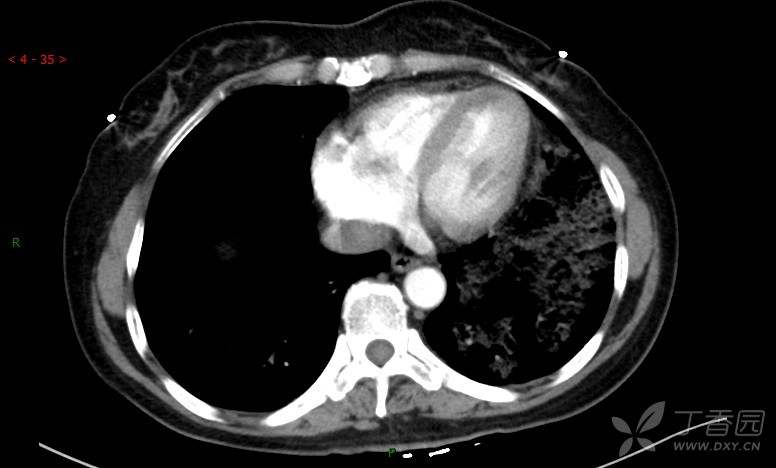

腺泡结节影,蜂窝征,这些都在提示……(病例3连发,附其他2例链接,病理已公布)

原帖名:胸部典型病例3(病例3连发,附其他2例链接)

咳嗽1年余,加重7天。

患者于1年余前始受凉后出现咳嗽,多为干咳,未在意,未到医院就诊。近3月患者出现咳痰,多为黄色粘痰,量大,伴乏力,偶有头晕、心慌,无发热、胸痛、憋喘,无低热、盗汗、咯血、胸痛,无头痛,无恶心、呕吐、腹痛、腹泻,无尿频、尿急、尿痛,在当地诊所给予抗感染等对症支持治疗(具体药物及剂量不详),症状仍时有反复。患者于1月余前到外院就诊,行胸部CT提示双肺炎症,左肺重,考虑为“间质性肺炎”,给予“左氧氟沙星、利巴韦林、头孢哌酮舒巴坦钠注射液”治疗,复查胸部CT示病灶吸收不理想,后出院继续于诊所对症治疗(具体药物及剂量不详),效果欠佳。7天前患者无明显诱因出现上述症状加重,为求进一步诊治,特来我院就诊,我院门诊以“肺炎(重症)?”收入留观室,留观室给予“盐酸莫西沙星氯化钠”等对症治疗后,今日转入我科。患者自发病以来,神志清,精神差,饮食正常,睡眠增多,大小便正常,体重近3月减轻5公斤余。